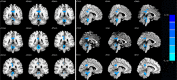

Results: Relative to the healthy controls, patients with anti-NMDAR encephalitis performed inferiorly in the MoCA score, and showed anxiety and depression disorders with higher HAMA and HAMD24 scores (all p < 0.05). In the brain functional activity analysis, the patients showed decreased ALFF values in the bilateral posterior cingulate gyrus, left precuneus, and bilateral cerebellum (false- discovery- rate corrected, p < 0.05). Furthermore, relative to the control group, the patients showed significantly increased FC between the left posterior cingulate cortex (PCC) and the bilateral lingual gyrus, right calcarine, right cuneus, also between the right PCC and the right fusiform gyrus, bilateral lingual gyrus, left calcarine, left cuneus, and right posterior central gyrus (false- discovery- rate corrected, p < 0.05). FC strength between the left posterior cingulate gyrus and right cuneus, and between the right posterior cingulate gyrus and left cuneus were both positively correlated with MoCA memory scores (r = 0.485, p = 0.048; r = 0.550, p = 0.022).